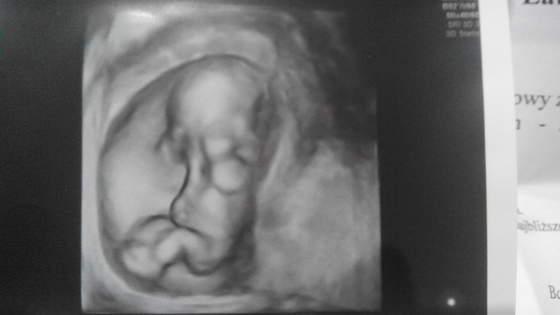

Hej dziewczyny ja również jestem dziś po wizycie usg czyli badaniu genetycznym jestem taka szczęśliwa bo napatrzałam się na dzidziusia a on tak ładnie wyglądał oczka zasłaniał troszkę piąstakmi a córcia się dziwiła że wygląda jakby płakał albo wstydził się. Taki słodki widok :) Ogólnie to termin wyszedł na 1 czerwca córcia może mieć prezent na dzień dziecka :)

IMG_20151126_182114.jpg

• IMG_20151126_182114.jpg

10,6 KB · Wyświetleń: 108

Ale wspaniale zdjecia <3